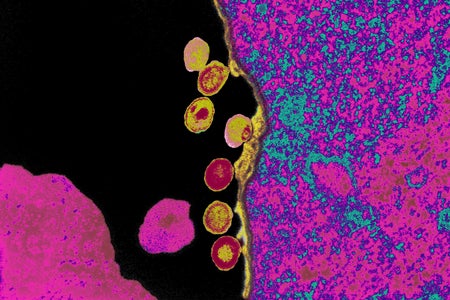

Another Patient Is Free of HIV after Receiving Virus-Resistant Cells

The risks associated with a bone marrow transplant used to treat HIV mean the procedure is unlikely to be widely used in its current form